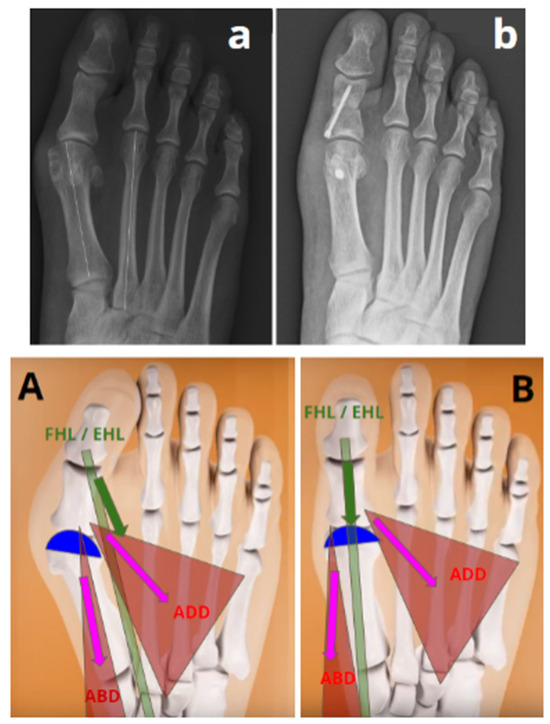

- Step 3: Chevron osteotomy (Figure 1). The dorsal cut was vertical, made 3 mm proximal to the distal articular surface of the M1, orthogonal to the axis of the 2nd metatarsal and extended over the dorsal third of the M1 head. The plantar cut began at the end of the dorsal cut and ended at the level of the neck of the M1 with an angulation of approximately 120°. The orientation of the saw in the dorsoplantar plane was aligned with the 4th metatarsal.

- Step 4: Sectioning of the lateral metatarso-sesamoid ligament (i.e., suspensory ligament) through osteotomy. The phalangeal and lateral sesamoid insertions of the conjoined tendon of the adductor muscle were not severed.

- Step 5: in the plantar part of the osteotomy, a medial wedge resection extending across the entire width of M1, with a Akin osteotomy thickness of 3 mm at its base, was performed, allowing for a supination movement of the head (Figure 2).